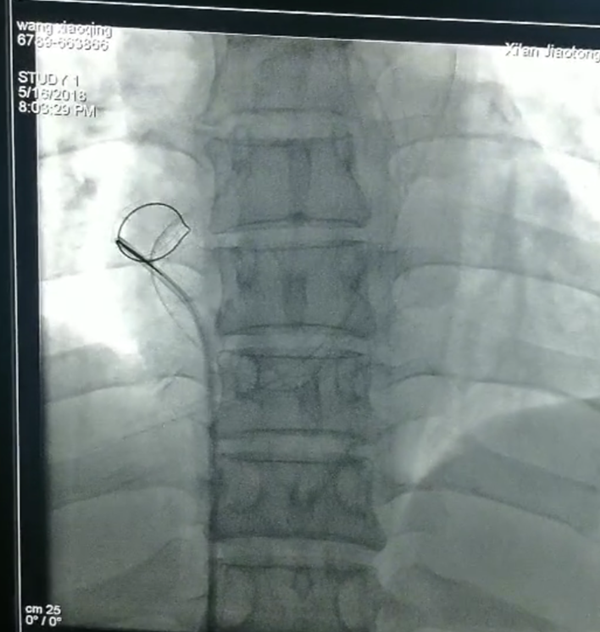

抓捕神器到位,看你哪里逃?

消毒铺巾以最快速度完成,穿刺,确认部位,放入网篮导丝,寻找断裂残端,小心翼翼拉出断裂的导管,一整套手法,董新教授前后用了仅十余分钟!断裂体内的导管直径约1.5mm,长约41mm,管子抓出来那一刻全体欢呼雀跃,掌声一片。